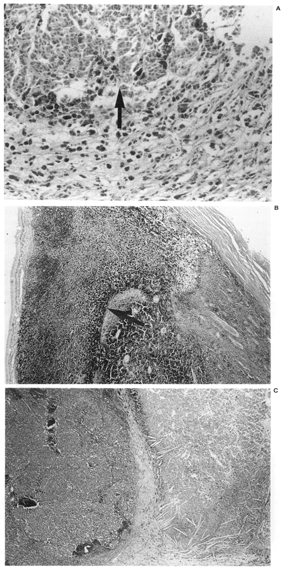

2. The presence, extent, and pattern of tumor necrosis were noted. The pattern of necrosis was identified as involving individual cells (Fig. 1) or as patchy when there were areas of necrotic cells scattered throughout the tumor (Fig. 2), or as geographic when confluent areas of the tumor were necrotic (Fig. 3). In each case, the extent of necrosis in the examined section was also recorded as <25%, 25-50%, >50-75% or >75% (Fig. 3).

Figure 2

FIG. 2. A: Patchy necrosis with islands of necrotic cells (arrows) RPT. B: Preoperative external beam radiotherapy; C: Enucleation alone eye. (Hematoxylin and eosin; Fig. A: X200, 87-781; Fig. B: X200, 86-1248; Fig. C: X200, 82-1391.)